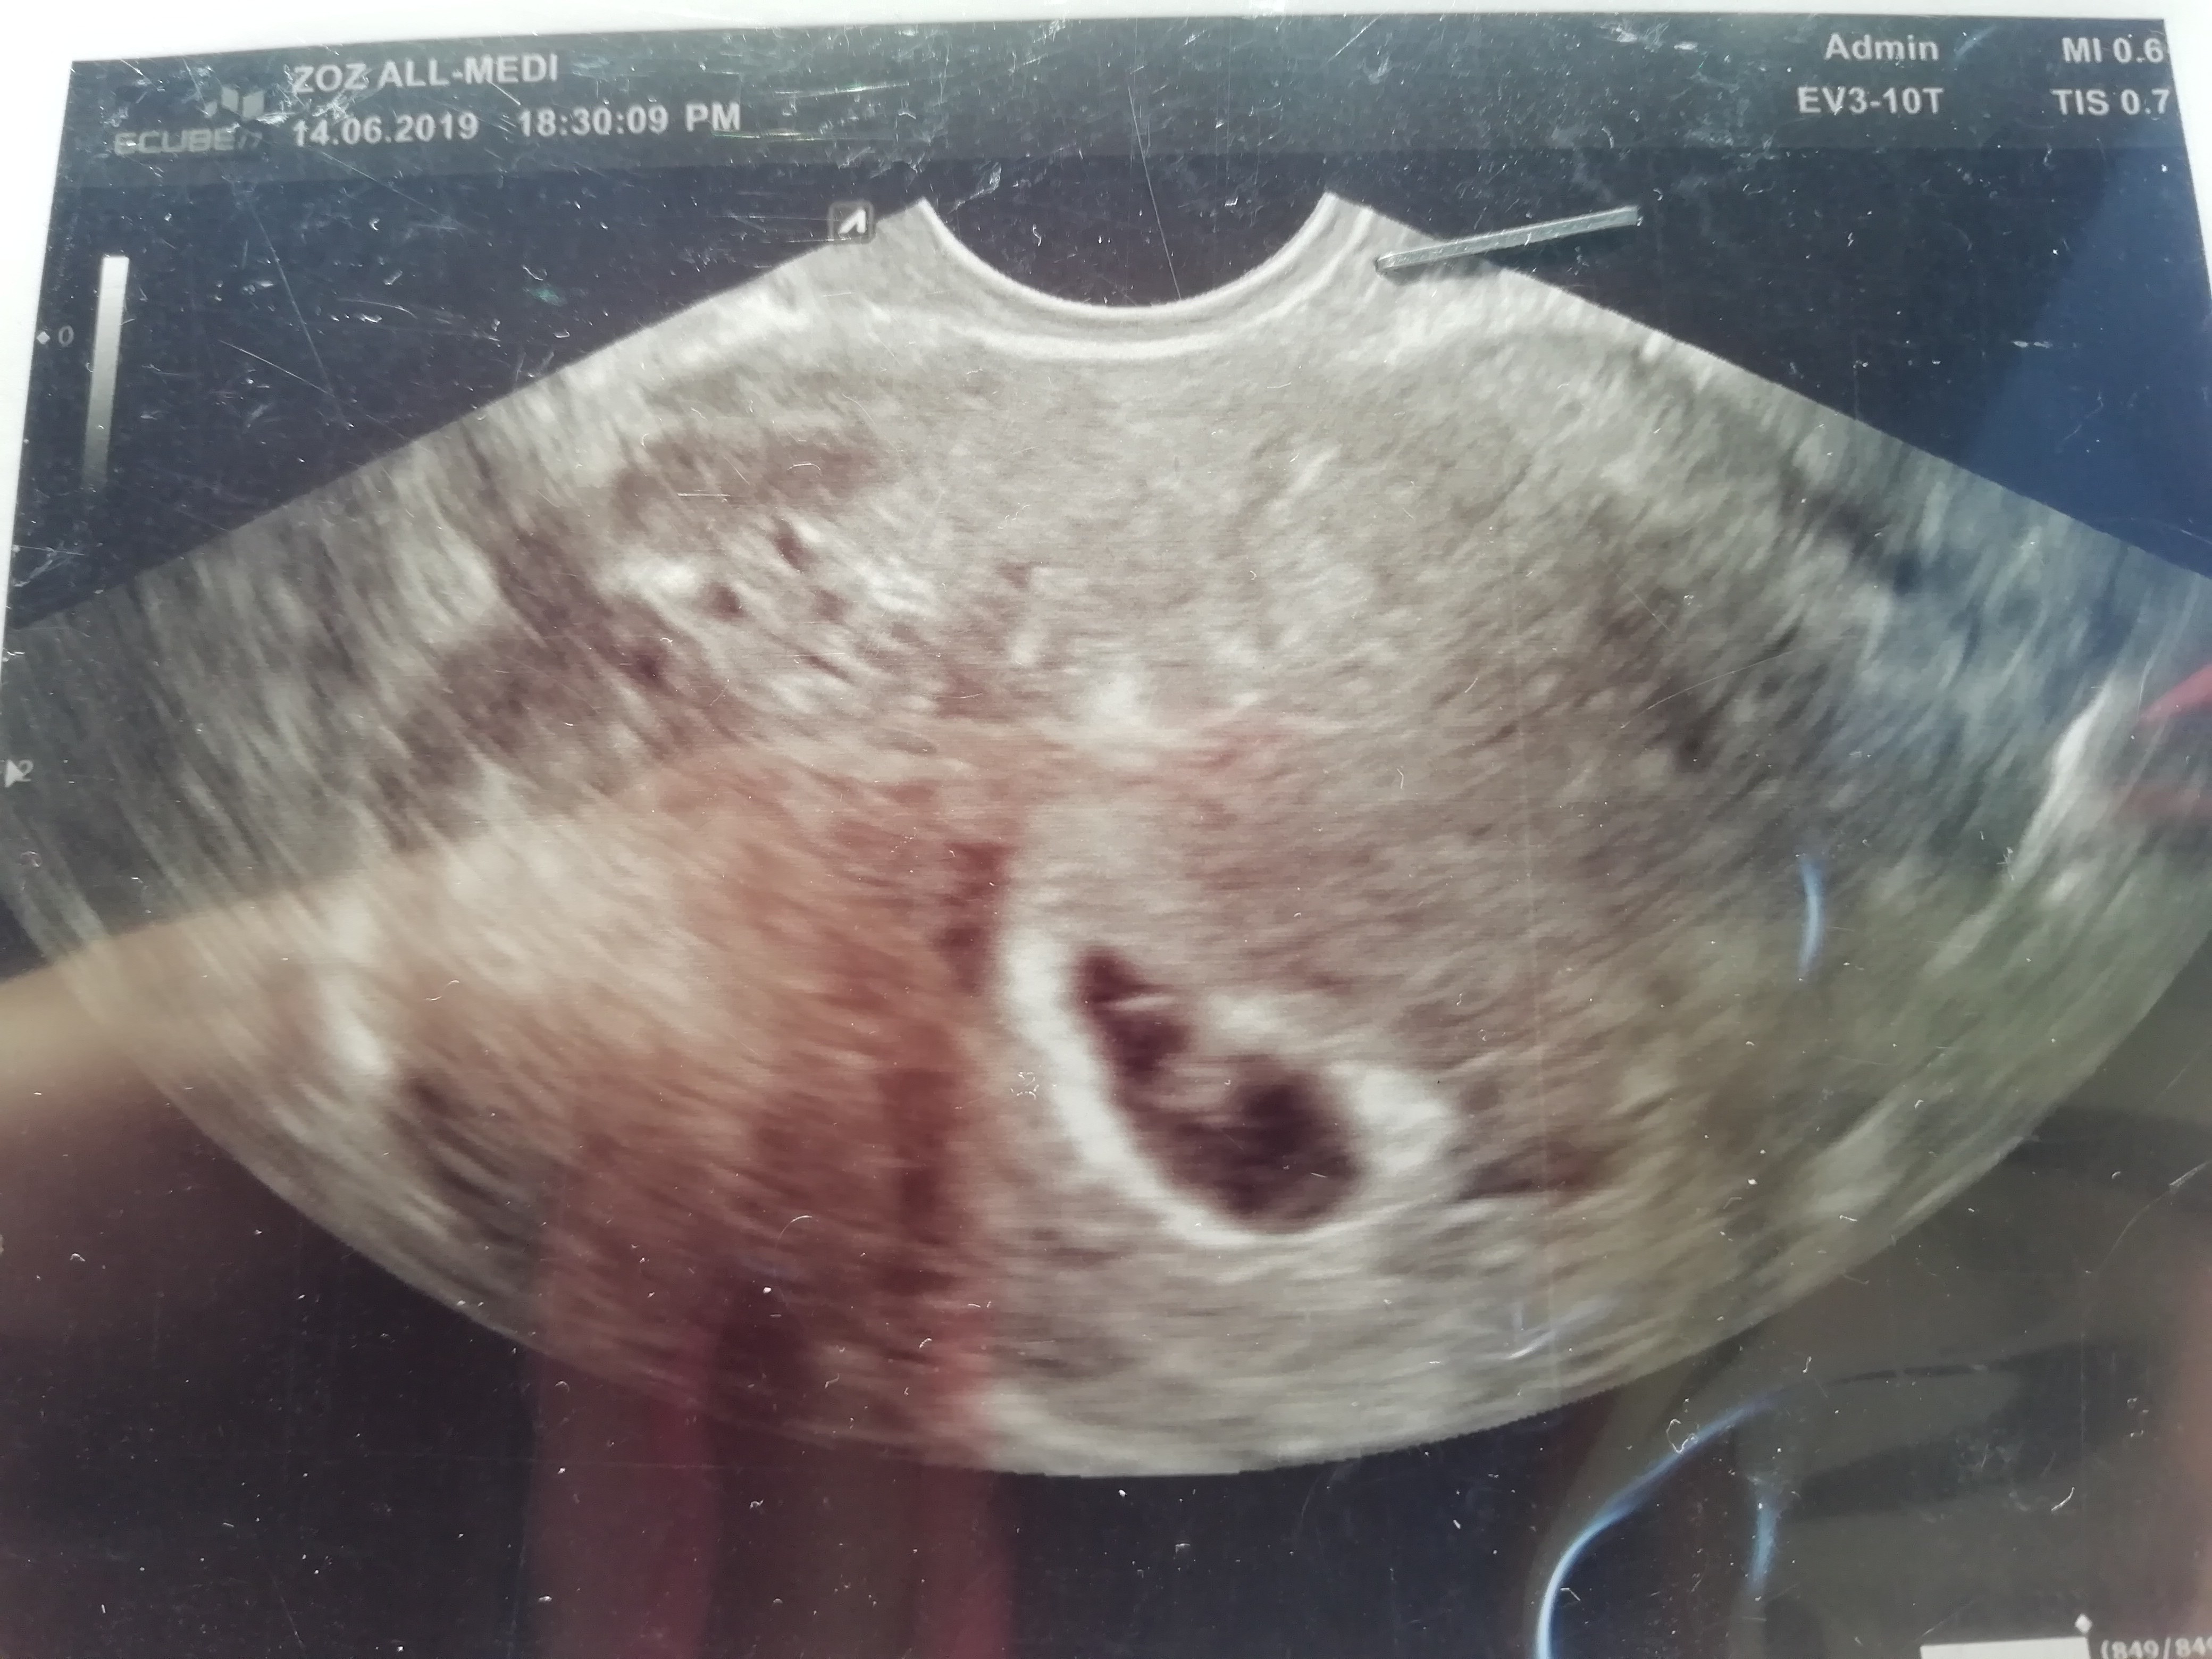

Ja juz jestem po wizycie Przedstawiam Wam nasza 6 tygodniowo kropeczke. Mąż był że mną, widział bicie serduszka [emoji4] mam już mega spokojna głowę. [emoji4] Zobacz załącznik 985779

Ja też po wizycie, jest dzidzia i bijące serduszko6t3d z usg z OM 7t6, ale spodziewałam się tego, owulacja była później

Wg Om 6+3tJotka super fotka gratuluje serduszka[emoji177] który u ciebie dokładnie TC?